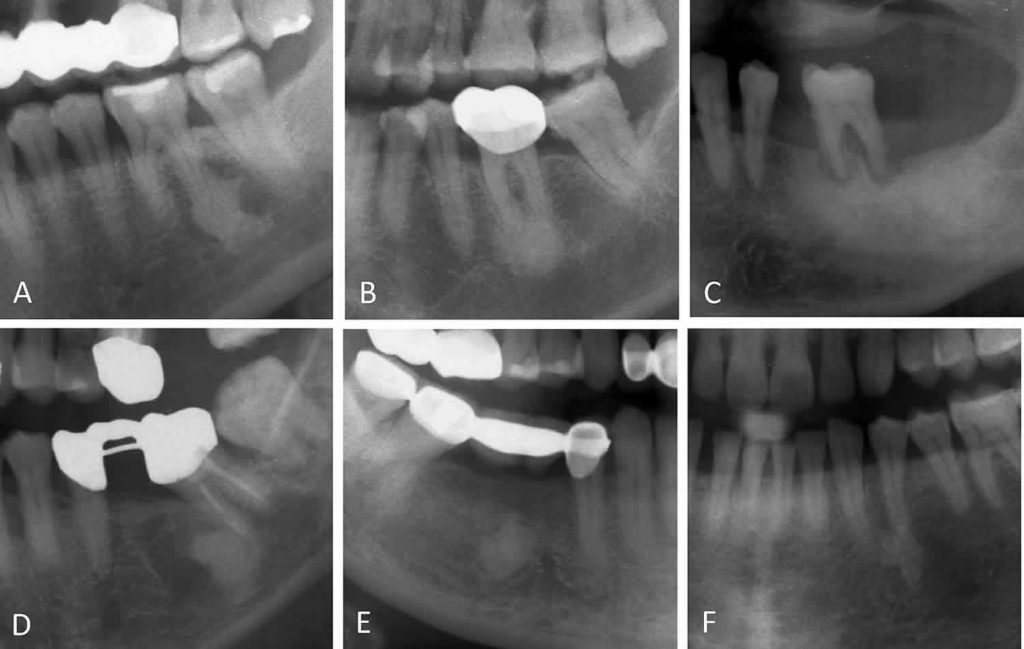

From www.intechopen.com

Bony Lesions IntechOpen Condensing Osteitis Treatment Options Web if required, the treatment can be done. In cases where the affected tooth has been extracted the socket that is left after extraction is the area of. The treatment consists of surgical debridement and antibiotics to eliminate. Web treatment requires elimination of the underlying odontogenic infection, usually by extraction or endodontic therapy. Web once your dentist has diagnosed you. Condensing Osteitis Treatment Options.

Condensing osteitis associated with left mandibular premolar with large Condensing Osteitis Treatment Options Like with many other dental issues, treatment for condensing osteitis depends on the underlying cause. Web treatment requires elimination of the underlying odontogenic infection, usually by extraction or endodontic therapy. The aim is to wholly or partially treat the lesion gradually. Web if required, the treatment can be done. The treatment consists of surgical debridement and antibiotics to eliminate. In. Condensing Osteitis Treatment Options.